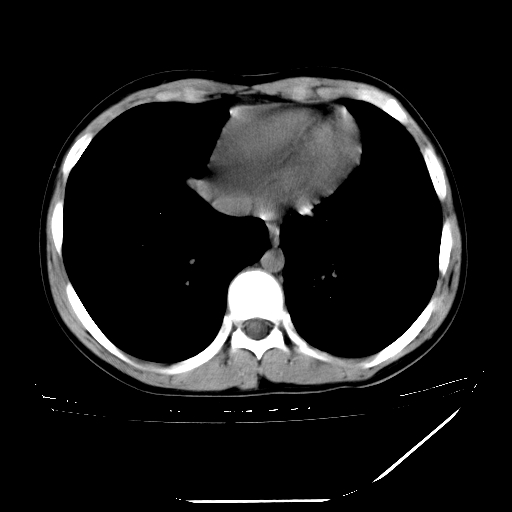

男,13岁,咳嗽、咳痰伴发热一周。

中上纵隔见多枚淋巴结肿大,部分相互融合成团片,左肺门增大,上叶支气管变窄,肺内多处斑片状 索条状及棉絮状致密影。临床“男,13岁,咳嗽、咳痰伴发热一周。”首先考虑:原发综合征!不除外淋巴瘤可能!

纵隔多发肿大淋巴结,部份有融合改变。双肺血管气管束增厚,以肺门为中心向外周散发,以左肺下叶为明显。考虑淋巴瘤可能性大。不除外原发综合征。

中上纵隔见多枚淋巴结肿大,部分相互融合成团片,左肺门增大,上叶支气管变窄,左肺支气管血管束增粗,可见磨玻璃样影。临床“男,13岁,咳嗽、咳痰伴发热一周。”首先考虑:淋巴瘤可能性大!

中上纵隔见多枚淋巴结肿大,部分相互融合成团片,纵隔内脂肪间隙模糊,左肺门增大,上叶支气管变窄,左肺支气管血管束增粗,可见磨玻璃样影。考虑纵隔淋巴管炎